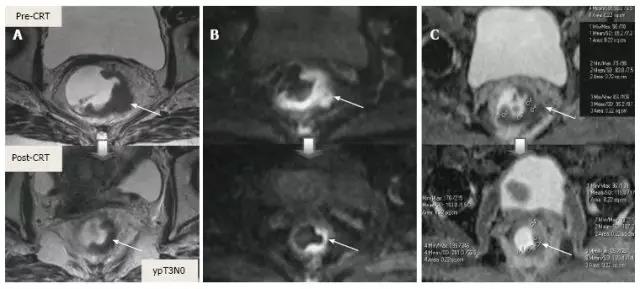

除了形态学发现之外,DWI 可以提供与细胞水平相关的功能信息变化。CRT 后细胞密度减低、纤维化或坏死使弥散加强,从而降低弥散加强图像的弥散信号强度,并增加在 ADC 图像 [ADC 值和 ADC 的信号强度(图 18 和图 19)。

虽然 DWI 能从纤维化中区分活的肿瘤细胞,也能区分治疗反应好与差,但不能预测完全缓解(图 20)。而且 CRT 后不能使用 DWI 评估肿瘤反应,因为即便在治疗前此类肿瘤也显示为 ADC 高密度(图 21)。

图 18. DWI 对放化疗后为 ypT3 的肿瘤重新分期。A. T2 加权轴位显示治疗后半圆形浸润肿瘤,与残留的 T3 肿瘤相符(箭头);B. 治疗后 DWI;C. ADC,图像分别对应肿瘤的高低信号强度,治疗前后 ADC 值分别为 0.68-0.72 和 1.22-1.44×10-3 mm²/s,治疗后 ADC 值增加与治疗反应相符。